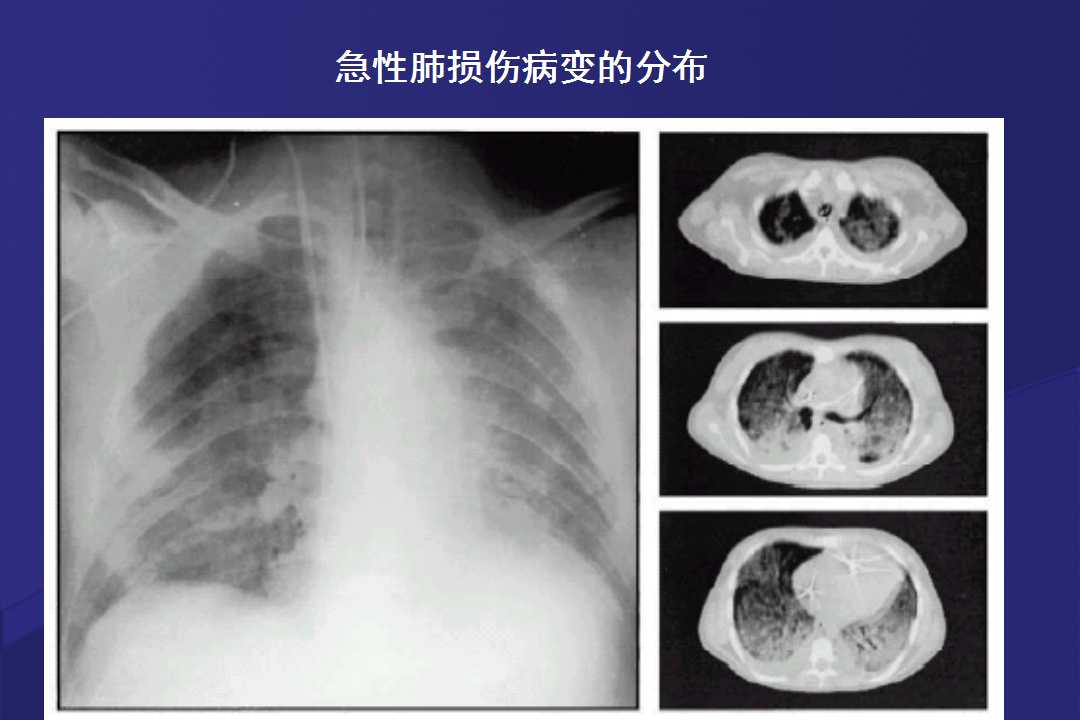

血液疾病患者肺部并发症影像学表现